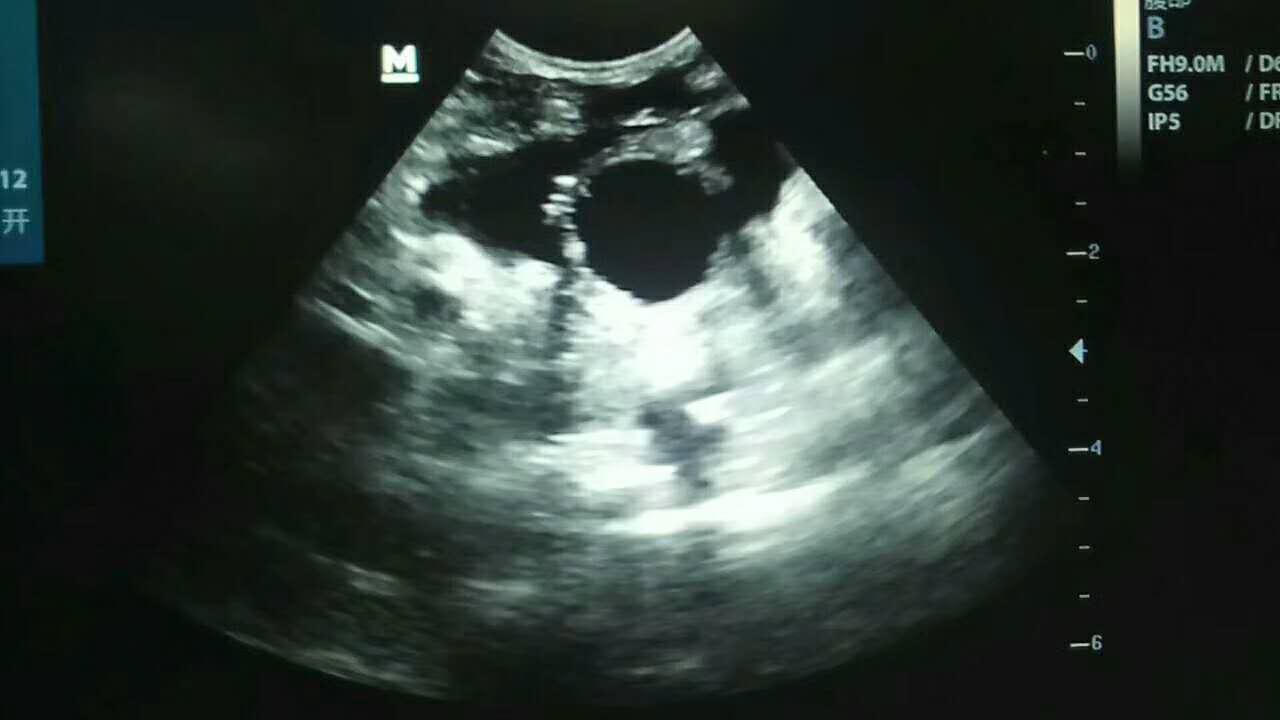

車禍導(dǎo)致膀胱破裂實(shí)施手術(shù):      小花,田園犬,母,前天被電動(dòng)車撞傷,腹腔積液/脹大,牙齦顏色粉紅   無食欲,喝水,主人不確定有沒有見尿,經(jīng)DR,B超等化驗(yàn)發(fā)現(xiàn)膀胱較小,膀胱完整性缺失,初步診斷膀胱破裂,實(shí)施手術(shù)修復(fù)   已蘇醒,狀態(tài)穩(wěn)定